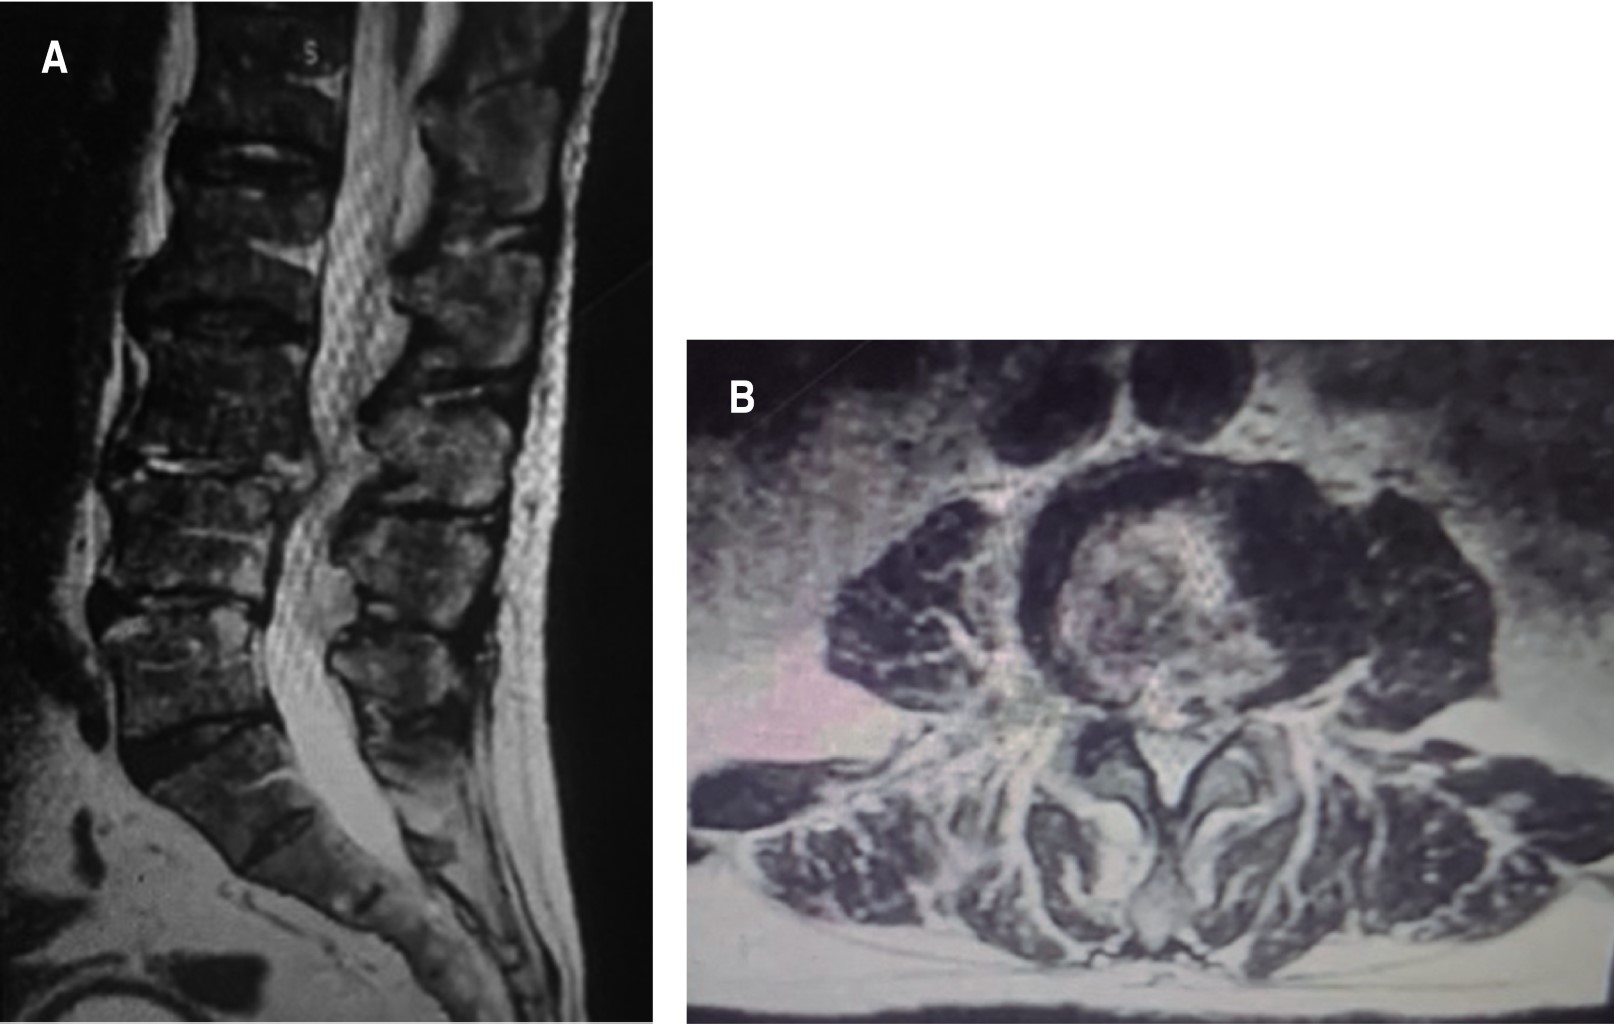

Figura 4